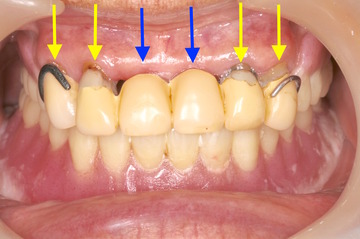

ケース NO.1 ⬆︎ 残した歯 ⬆︎ 抜いた歯

上が総入れ歯、下がレジリエンツテレスコープ義歯です。